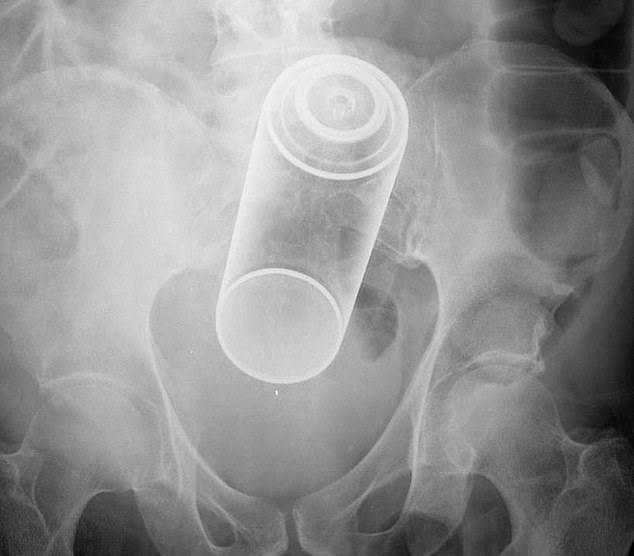

It was found that the rectum is the most common place for bizarre items to get stuck. Some of the objects include household items such as aerosol can, plastic pill bottle, beer bottle, and a plastic cigar holder.

- ‘Took a soda bottle with fireball whiskey via his rectum, stuck bottle in rectum and squeezed.’